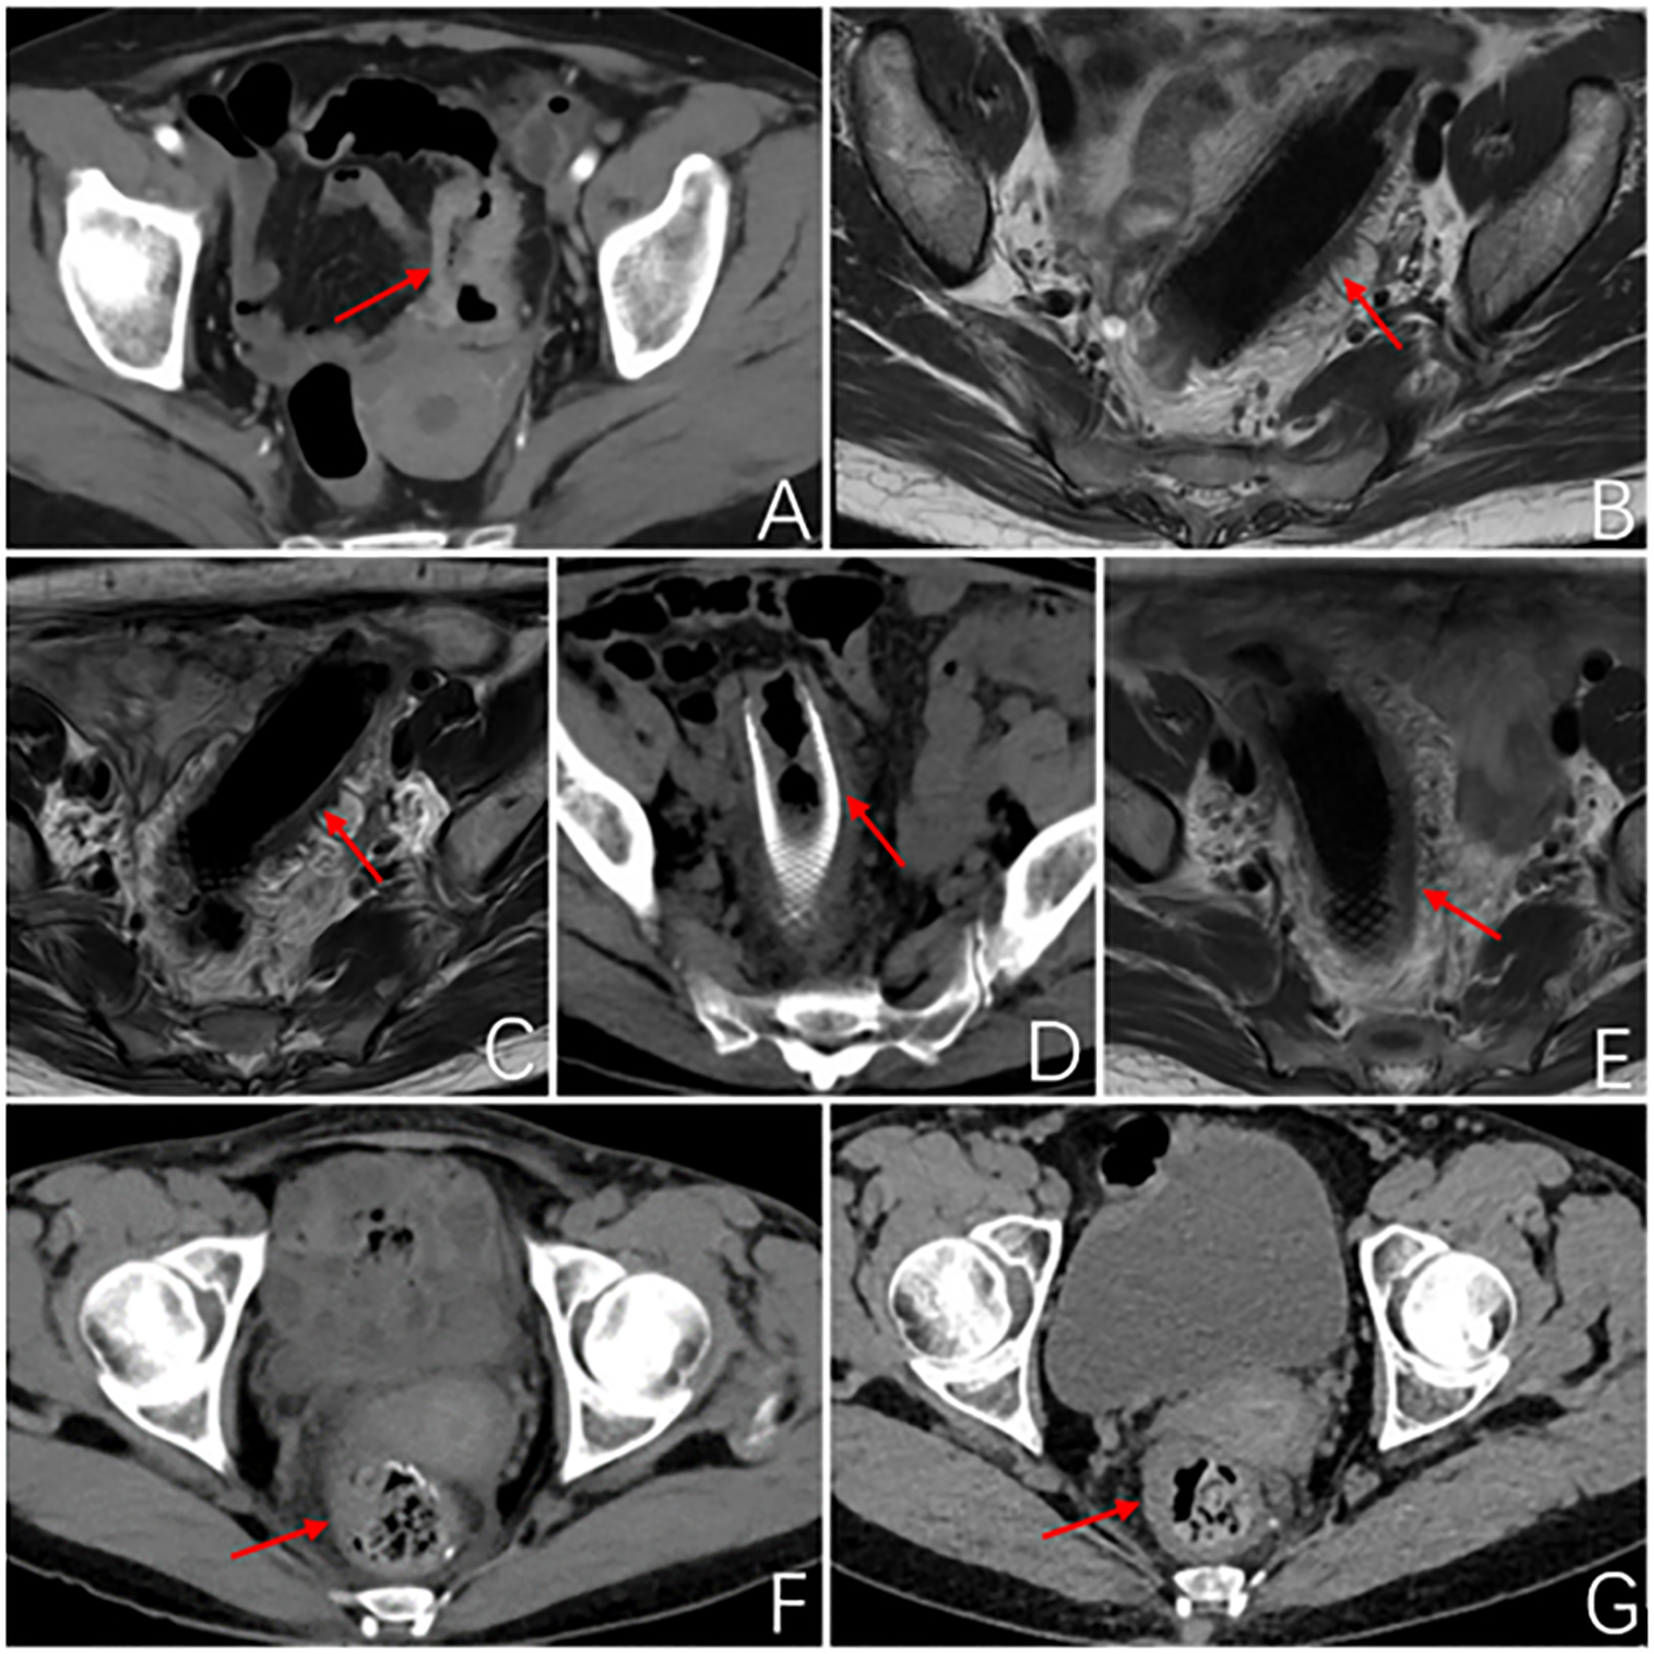

The patient, female, 51 years old, was admitted to our hospital on December 6, 2022 for “difficulty in defecation for more than 3 months”. The enhanced Computed Tomography (CT) examination of abdomen showed: sigmoid colon cancer, preliminary stage T4N1 (Figure 1). Enteroscopy showed: the colonoscope reached a depth of 20cm and revealed an elevated lesion causing luminal constriction, impeding further advancement of the scope. The lesion exhibited a firm texture with a constrictive growth pattern and surface ulceration (Supplementary Figure 1). The pathological examination results revealed the presence of moderately differentiated adenocarcinoma in the colon (Figure 2). Immunohistochemical staining results showed that the cancer cells expressed CK8/18(+), p53 (mutant), Syn(-), and had high expression of Ki-67 (70%+).Genetic testing results: K-RAS gene: wild type; N-RAS gene: wild type; B-Raf gene: wild type. After multidisciplinary discussion, it was recommended that the patient undergo PDT as an effective intervention for alleviating the existing obstruction.

Figure 1

Imageological examination. (A) Abdominal enhanced CT at first admission: The local wall of the sigmoid colon shows circumferential thickening with mild enhancement, resulting in a narrow lumen and roughness around the wall. Consider sigmoid colon cancer, preliminary staging T4N1. (B) MR rectal scan after 3 months of PDT: The image shows a metallic internal fixator within the lumen of the sigmoid colon, with corresponding mild thickening of the intestinal wall. The proximal and distal ends of the stent exhibit uneven thickening of the intestinal wall that protrudes into the lumen. (C) MR rectal scan 4.5 months after PDT: Within the lumen of the sigmoid colon, a metallic internal fixator shadow is visible. Mild thickening of the bowel wall where the stent is located, uneven thickening of the bowel wall proximal and distal to the stent and protruding into the lumen, proximal luminal stenosis slightly better than before. (D) Abdominal CT 6 months after photodynamic surgery: After colonic stent placement, thickening of the wall and grossness of the tube is seen. (E) MR Rectal plain scan 6 months after photodynamic operation: Changes after colonic stent placement, uneven thickening of the proximal and distal bowel wall of the stent and protruding into the lumen, this time the proximal and distal bowel wall of the stent thickened to a lesser extent. (F) Abdominal CT 2 months after robotic surgery: No obvious abnormal thickening of the anastomotic wall after radical surgery for colon cancer. (G) Abdominal CT 5 months after robotic surgery: After radical resection of colon cancer, the anastomotic wall does not thicken. The red arrows demonstrate the site of the tumor lesion, the location of the metal stent, and the postoperative anastomosis.

After PDT, combined with chemotherapy and immunotherapy, the patient’s tumor lesions significantly regressed. The difficulty in defecation improved noticeably. Preoperative MRI showed a reduction in the degree of intestinal wall thickening. The number of enlarged lymph nodes adjacent to the bilateral iliac vessels and inguinal region decreased compared to before treatment (Figure 1). After Multi-Disciplinary Treatment (MDT) discussion, the decision was made to perform fluorescent laparoscopic localization combined with robotic colon cancer resection. Preoperative colonoscopy of the tumor was performed on June 6, 2023, at a distance of 15-20 cm from the anus, tumor tissue was visible with a patent lumen, and 500 ul of indocyanine green was injected into the oral and anal sides of the lesion. After perfect preparation, radical resection of malignant tumor of colon with robotic assistance was performed. The duration of the surgical procedure was 215 minutes, with intraoperative blood loss measuring 20 ml. On the first postoperative day, drainage volume reached 150 ml, and a small amount of pelvic fluid was observed during the postoperative review. No other complications were occurred, and the patient achieved ambulation on the second postoperative day, and was fed with water on the fifth postoperative day. Postoperative pathological examination of the surgical specimen showed: 1. A small amount of residual well-differentiated adenocarcinoma component in the ulcerative lesion area, with cancer invasion into the subserosal layer (pT3), without definite involvement of blood vessels or nerves; tumor regression grade (TRG): Grade 1 (single or small foci of residual cells) (Figure 2); no cancer invasion in the resected margins on both sides. 2. Immunohistochemical staining confirmed that there was no lymph node metastasis (0/24); immunohistochemistry staining results: cancer cells CK8/18+,Syn-, CgA-, p53 (+), C-erbB-2 (0), Ki67 (40%+); MLH1+, PMS-2+, MSH-2+, MSH-6+.